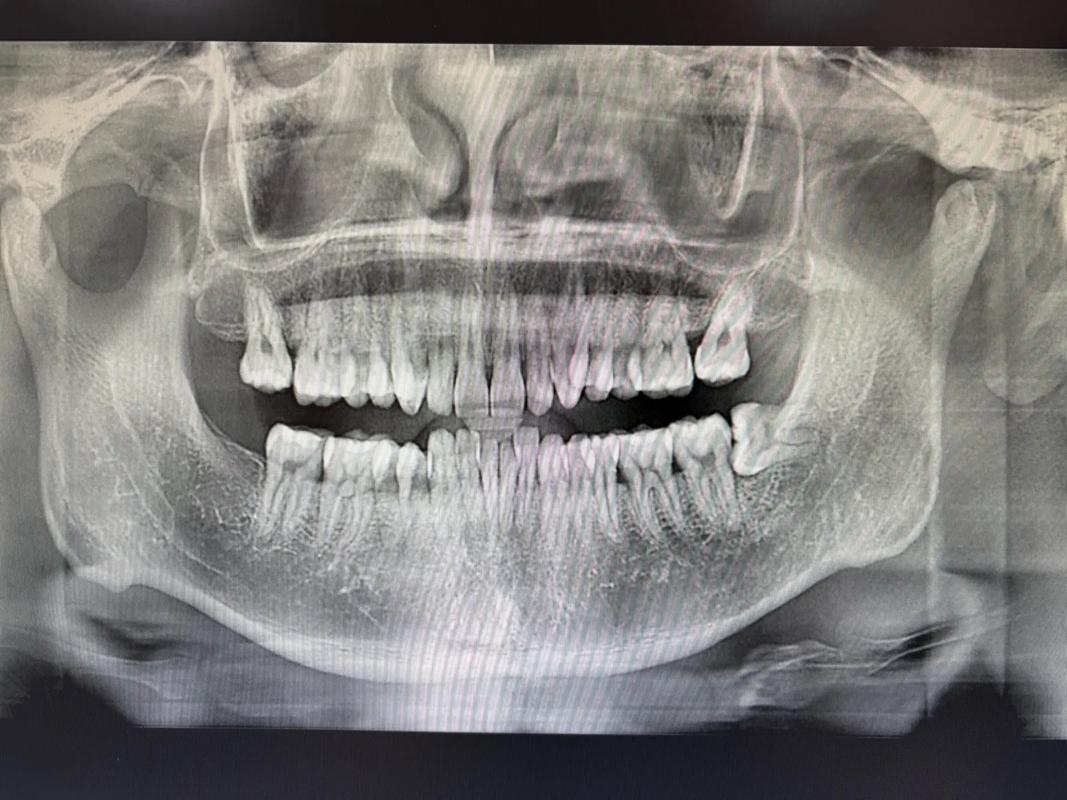

- X光片监测的重要性:曲面断层片或CBCT(锥形束CT)是评估未萌智齿的“金标准”,可清晰显示智齿位置、方向、与邻牙关系及骨内情况,医生需根据影像结果判断风险。